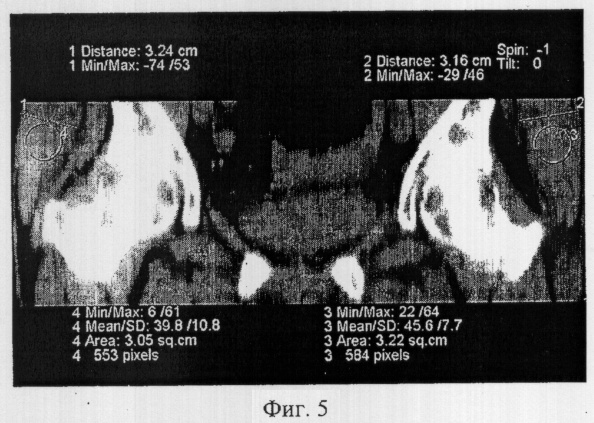

Фиг.5 иллюстрирует проведение измерений толщины и плотности, мышечных брюшек по мультипланарным реконструкциям в плоскостях, соответствующих ходу мышечных пучков средних ягодичных мышц в парафронтальной плоскости;

Обработку аксиальных срезов проводят в режиме мультипланарной реконструкции в аксиальных, парааксиальных и продольных плоскостях, соответствующих ходу мышечных пучков. На полученных изображениях в интерактивном режиме высчитывают толщину, площадь поперечного сечения (см2) и плотность отдельных мышц в единицах Хаунсфильда (HU).

Обработку аксиальных срезов проводили в режиме мультипланарной реконструкции в аксиальных, парааксиальных и продольных плоскостях, соответствующих ходу мышечных пучков. На полученных изображениях в интерактивном режиме высчитывали толщину, площадь поперечного сечения (см) и плотность отдельных мышц в единицах Хаунсфильда (HU).

Выявлено снижение показателей толщины и площади поперечного сечения малой и средней ягодичных мышц до 60% от показателей мышц контралатерального сегмента. Определена выраженная жировая дистрофия мышечных волокон по резкому снижению показателей плотности мышц по шкале Хаунсфильда до значений плотности жировой ткани.